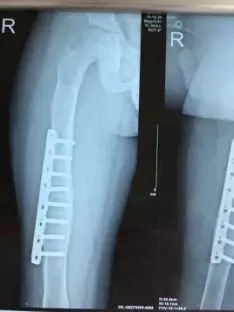

▲小桂手术X线片前后对比图

为了让小桂尽快恢复,深圳万丰医院骨科团队反复协商后制定专项方案,在获得家属认可后,患儿在腰硬联合麻醉下行右股骨骨折切开、探查、骨肿瘤病灶清除、骨折复位,然后实施骨折钢板螺钉内固定术。手术为时两小时,进展顺利。